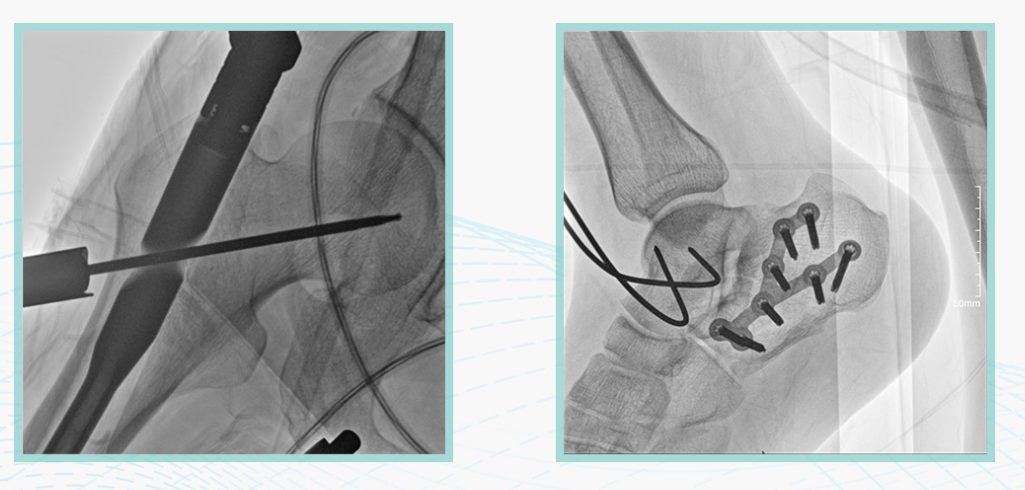

此外,骨科手术时间平均时长约为45分钟左右时间,长期的X线透视或摄影曝光剂量将对临床手术与操作医务工作者造成难以评估的健康风险,悦画通过支持摄影曝光参数的自主调节,可以保证在最低剂量水平下输出满足临床手术定位与引导所需要的影像质量,相较于市面上的固定曝光参数配置移动C臂,自主参数调节设计的曝光功能设计,可以大幅减少医务工作者的X线辐射剂量。

不仅如此,悦画在产品的剂量安全管理上,还支持DAP剂量实时显示与统计功能。为了减少误操作的X射线曝光,悦画具有X射线锁定保护功能,在摄影曝光停止后立即进行X射线曝光锁定,解锁后才能支持继续曝光,减少以往临床过程中医务工作者因为误操作所导致的额外X射线辐射。